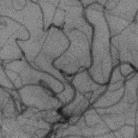

The rapid and accurate direct multi-frame interpolation method for Digital Subtraction Angiography (DSA) images is crucial for reducing radiation and providing real-time assistance to physicians for precise diagnostics and treatment. DSA images contain complex vascular structures and various motions. Applying natural scene Video Frame Interpolation (VFI) methods results in motion artifacts, structural dissipation, and blurriness. Recently, MoSt-DSA has specifically addressed these issues for the first time and achieved SOTA results. However, MoSt-DSA's focus on real-time performance leads to insufficient suppression of high-frequency noise and incomplete filtering of low-frequency noise in the generated images. To address these issues within the same computational time scale, we propose GaraMoSt. Specifically, we optimize the network pipeline with a parallel design and propose a module named MG-MSFE. MG-MSFE extracts frame-relative motion and structural features at various granularities in a fully convolutional parallel manner and supports independent, flexible adjustment of context-aware granularity at different scales, thus enhancing computational efficiency and accuracy. Extensive experiments demonstrate that GaraMoSt achieves the SOTA performance in accuracy, robustness, visual effects, and noise suppression, comprehensively surpassing MoSt-DSA and other natural scene VFI methods. The code and models are available at https://github.com/ZyoungXu/GaraMoSt.